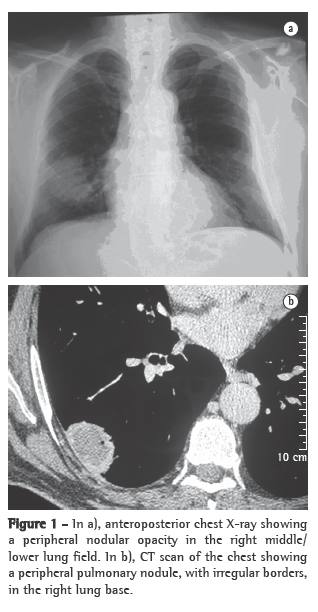

A 61-year-old male patient sought treatment at the pulmonology outpatient clinic reporting lung secretion with occasional bloody sputum for approximately 5 months. Within the past month, the patient had severe cough, dyspnea and a peak of fever. The patient reported no other respiratory problems and no history of occupational risk. He also reported long-term labyrinthitis and recent hypoacusis. He was a former smoker (30 pack-years) who had not smoked for 10 years. The physical examination revealed that the patient was well hydrated and with good color. He presented abnormal breath sounds, crackles in the right hemithorax base, increased vocal fremitus and a systemic arterial pressure of 120/80 mmHg. The SpO2 was 96%. The investigation began with imaging studies and laboratory tests. A chest X-ray showed a nodular opacity in the lower third of the right hemithorax (Figure 1a), a sinus X-ray revealed thickening of the left maxillary sinus mucosa, and a CT scan of the chest revealed an extensive lesion in the right hemithorax (4.2 cm × 3.1 cm), contiguous with the parietal pleura (Figure 1b). Based on these findings, we requested a tomography-guided percutaneous biopsy, which showed areas of fibrosis and areas of extensive necrosis associated with an inflammatory process (Figures 2a and 2b), whose possible causes include WG, bronchocentric granulomatosis or an infectious disease.

Imaging studies showed an extensive unilateral nodular lesion. This finding is uncommon in WG and, therefore, there was diagnostic difficulty in view of the possibility of a malignant disease. What is expected in this type of vasculitis is pulmonary infiltration or bilateral multiple nodules, which can be accompanied by cavitations (in 50% of the cases).(8) The next step was then to resort to tomography-guided percutaneous biopsy, a procedure that has high sensitivity, specificity and accuracy, the last ranging from 84.5% to 90%, depending directly on the size of the lesion. The principal reason for requesting the procedure is to determine malignancy in solid pulmonary lesions.(9,10)